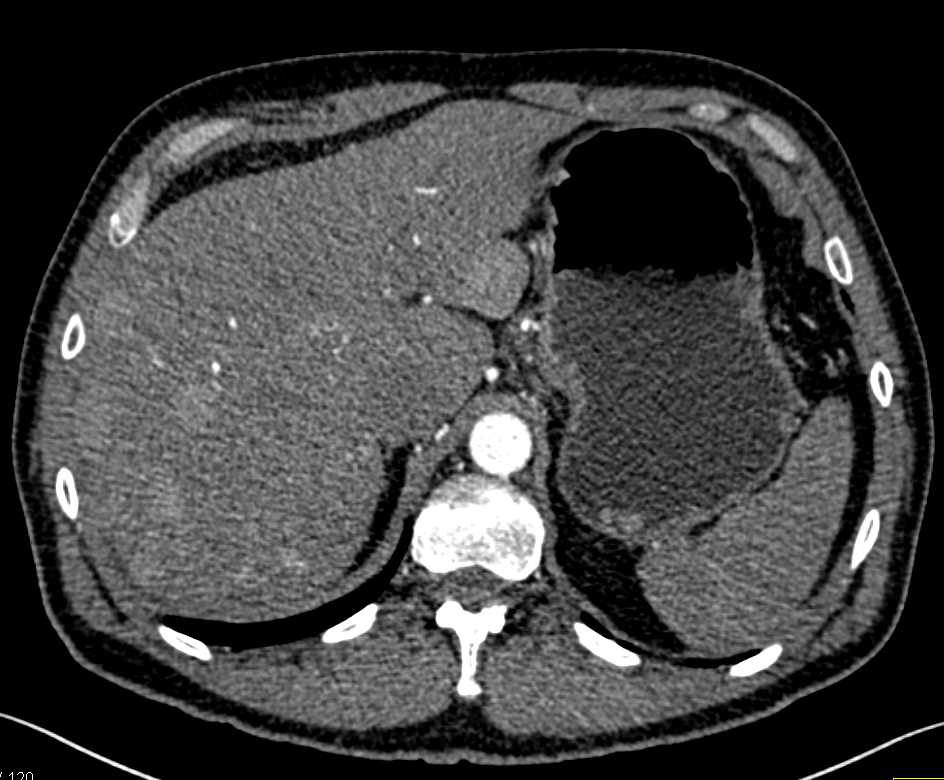

Liver Infarction Looks Like a Tumor